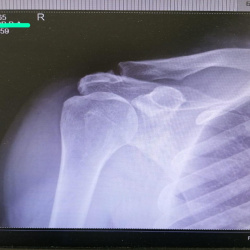

Коллеги, здравствуйте! Мужчина, 40 лет, жалобы на боли в правом коленном суставе.  По снимкам - много вопросов. 1) Что с бугристостью большеберцовой кости? Экзостоз? Вроде как...